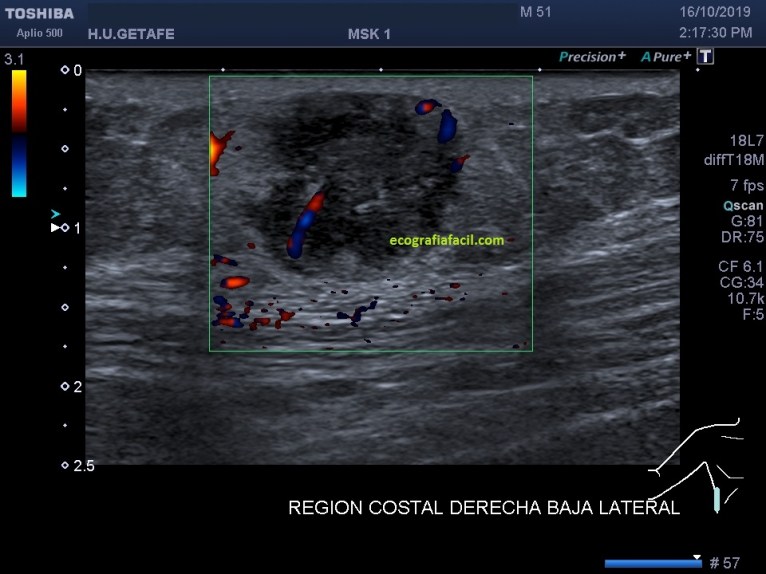

En la imagen 1 y 2, las medidas, básico en cualquier estudio de una lesión. La imagen 3 nos muestra la vascularización de la lesión, que lo está, aunque no es una vascularización exacerbada.

Tiene vascularización.